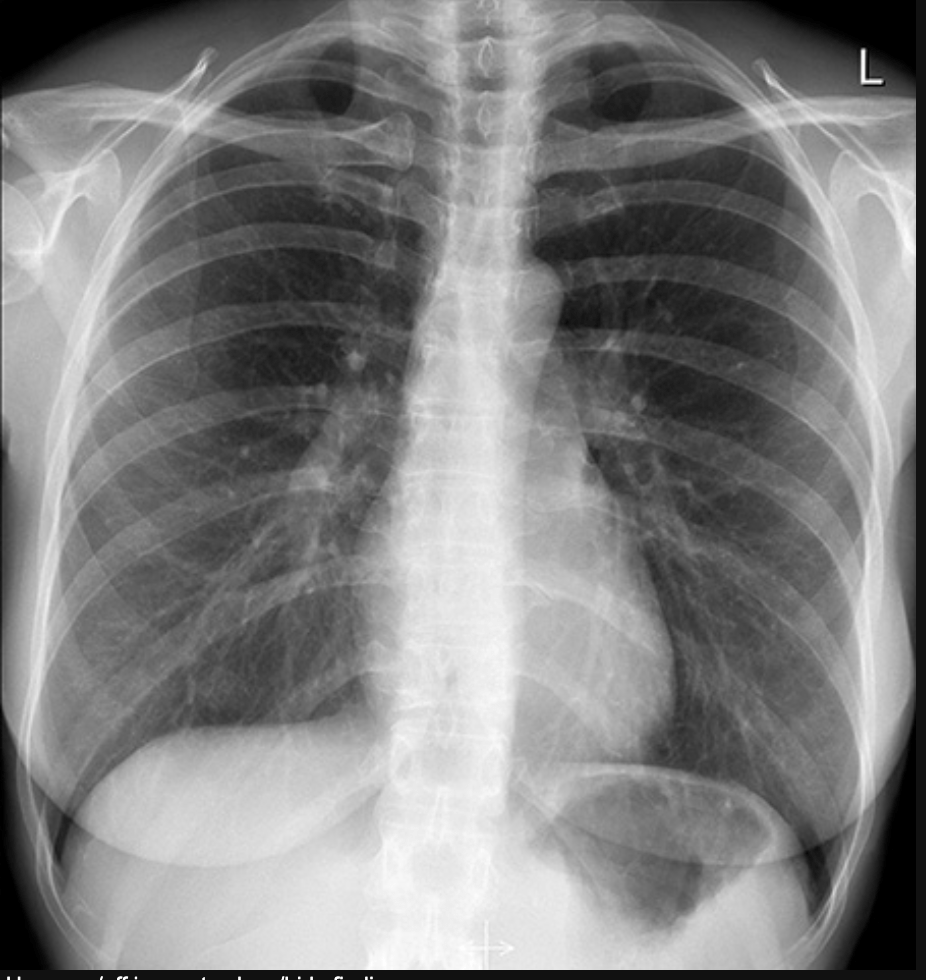

• Lets take this image for example.

• What do we see in it?